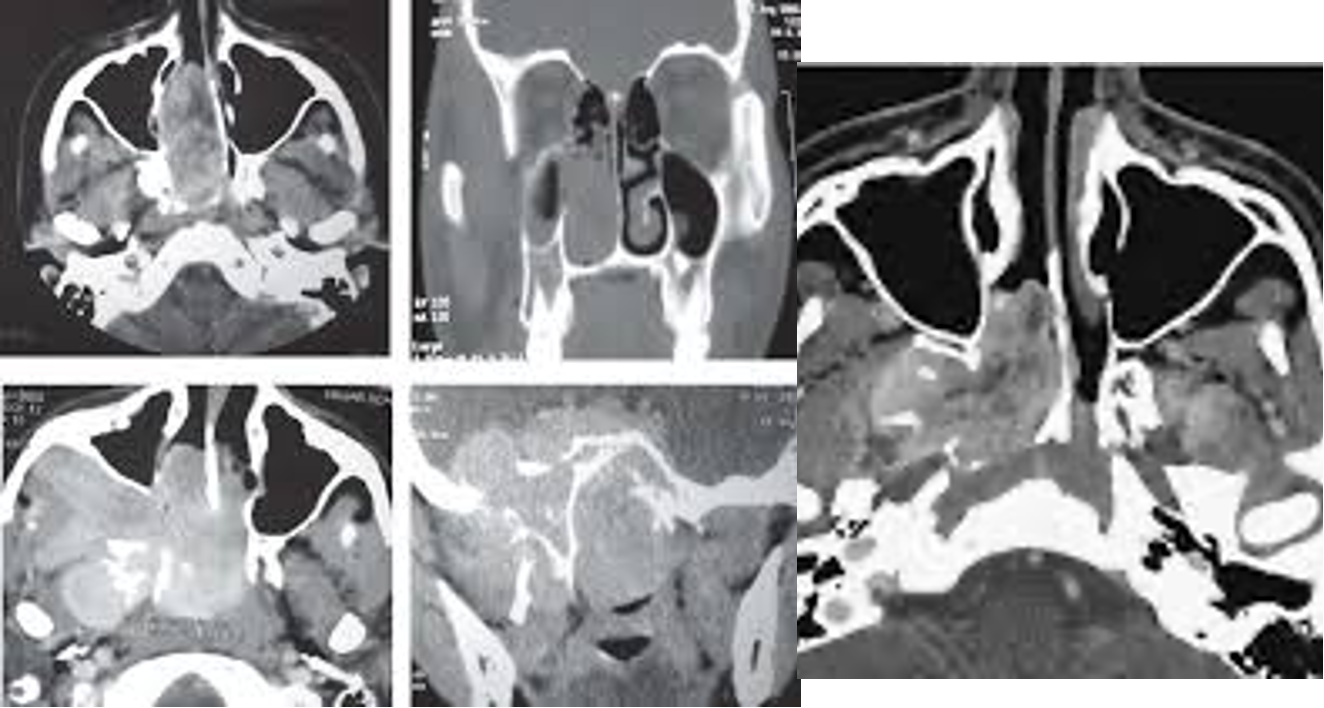

• Imaging: CT and MRI

• Angiography: Carotid angiography and MR angiography show feeding vessel of the tumor and allow preoperative embolization to minimize intraoperative bleeding.